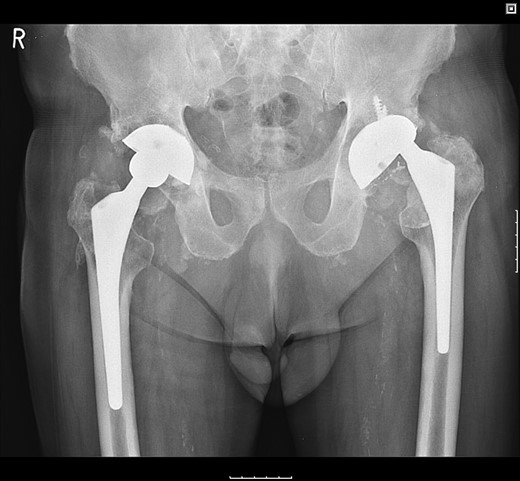

The patient was subsequently scheduled for revision surgery of the acetabular component. Intraoperatively, there was blackening of the periprosthetic tissue and metal debris throughout. The PE liner remained engaged within the acetabular cup with significant wear through its back. The femoral head had migrated superolaterally through the acetabular cup and was articulating with the superior acetabular wall causing bony destruction. The acetabular cup remained well fixed within the acetabulum with good bony ingrowth (Figs 2 and 3).

The acetabular component showing extreme wear-through and metallic fragments.